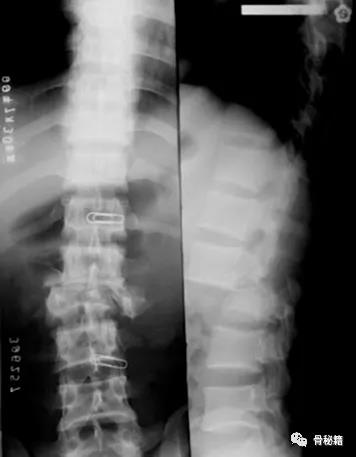

前后移位

对于前后移位就相对复杂一些1、解锁脊柱的关节面

如果坎墩严重,需要先植入椎弓根螺钉,咬除部分后方椎板,进行后柱的撑开。

先植入能植入的椎弓根螺钉, 深度过椎弓根即可

先进行短阶段的撑开,撑开之后暴露关键的前移的椎体再植入椎弓根螺钉进行二次撑开

要点:进行初次撑开之后,取下一侧的棒,植入关键椎体的椎弓根螺钉再换另外一侧,同法。

撑开时,可先用直棒,最后复位好了后再进行棒的塑性恢复腰椎前凸来达到较好的稳定

最后添加横联和植骨融合来增加稳定性